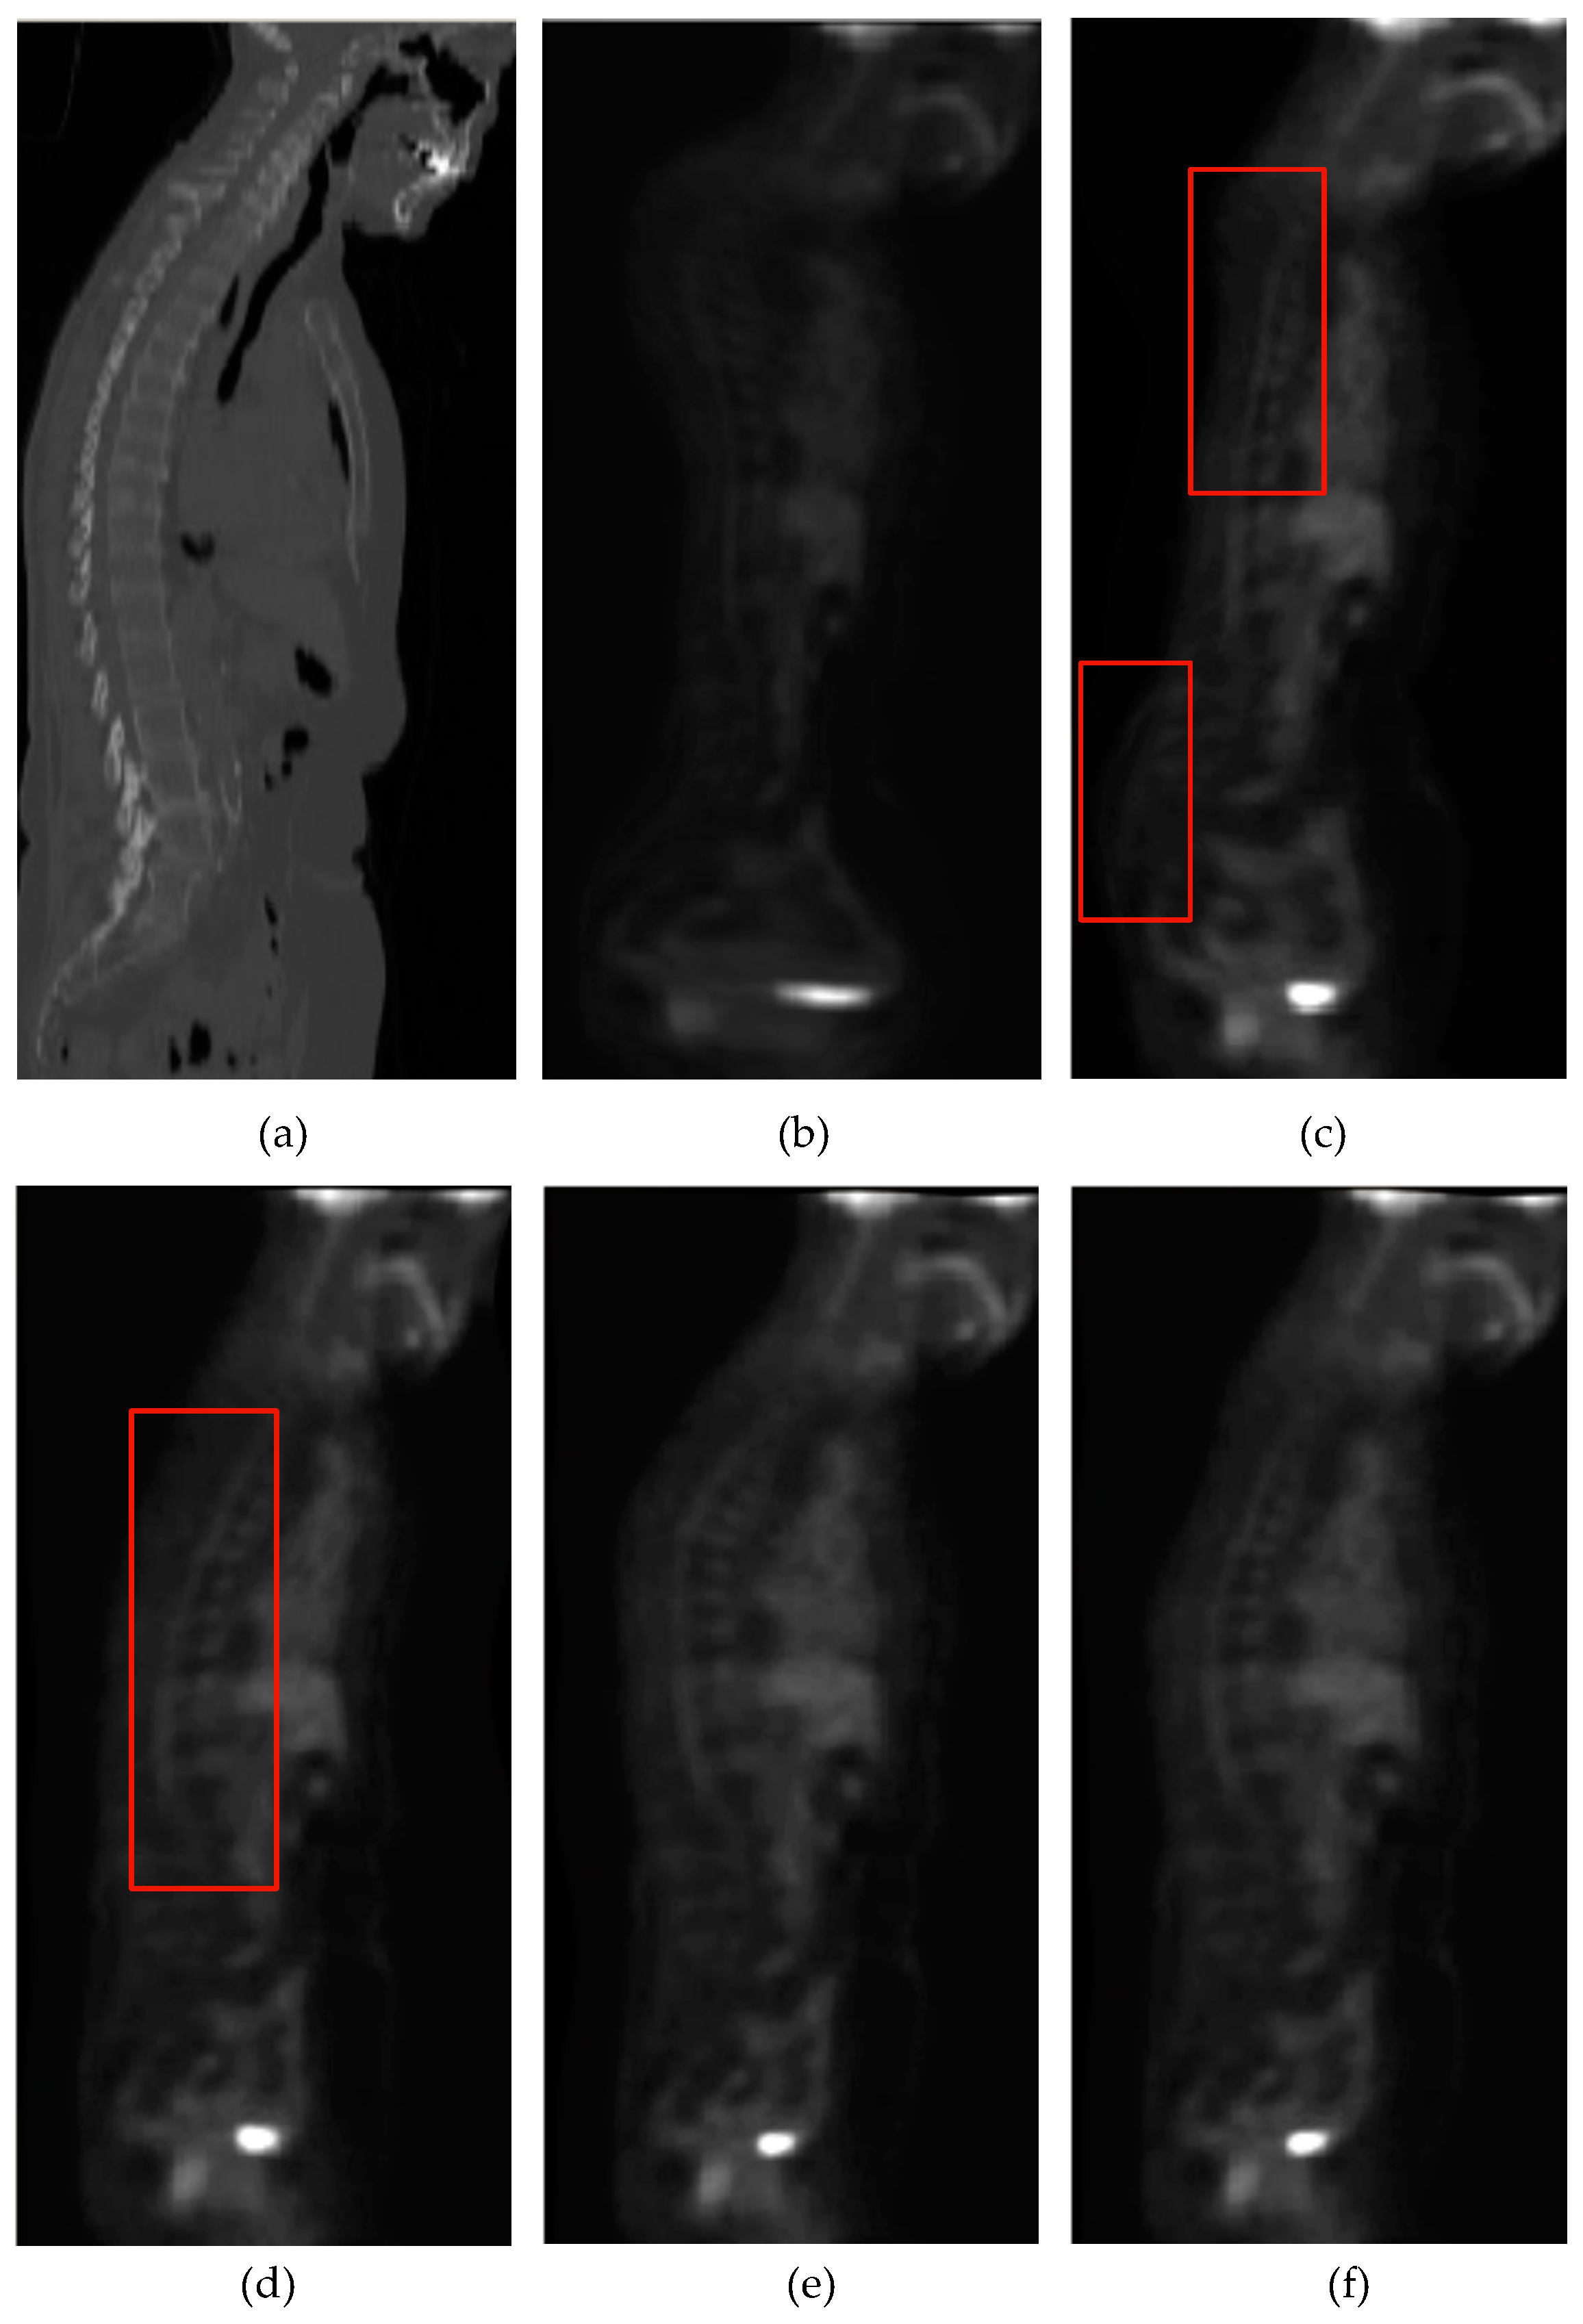

Figure 9 visually shows the registration results of 3D PD-T1 images for all the evaluated methods. Here, it should be noted that the background regions in these images are removed and the same operation will be implemented for other experiments in the rest of this paper. The comparison among Figure 9f and Figure 9c–e shows that the registration result of the FMIND method is more similar to the reference image that is shown in Figure 9a than those of the ESSD, MIND, and HLCSO methods. Especially for the tissue indicated by the red boxes in Figure 9, the FMIND can recover its deformation better than other evaluated methods.

Figure 9.

The registration results of all evaluated methods operating on 3D PD-T1 images. (a) PD image (reference image); (b) T1 image (float image); (c) ESSD; (d) MIND; (e) hybrid L-BFGS-B and cat swarm optimization (HLCSO); and, (f) FMIND.